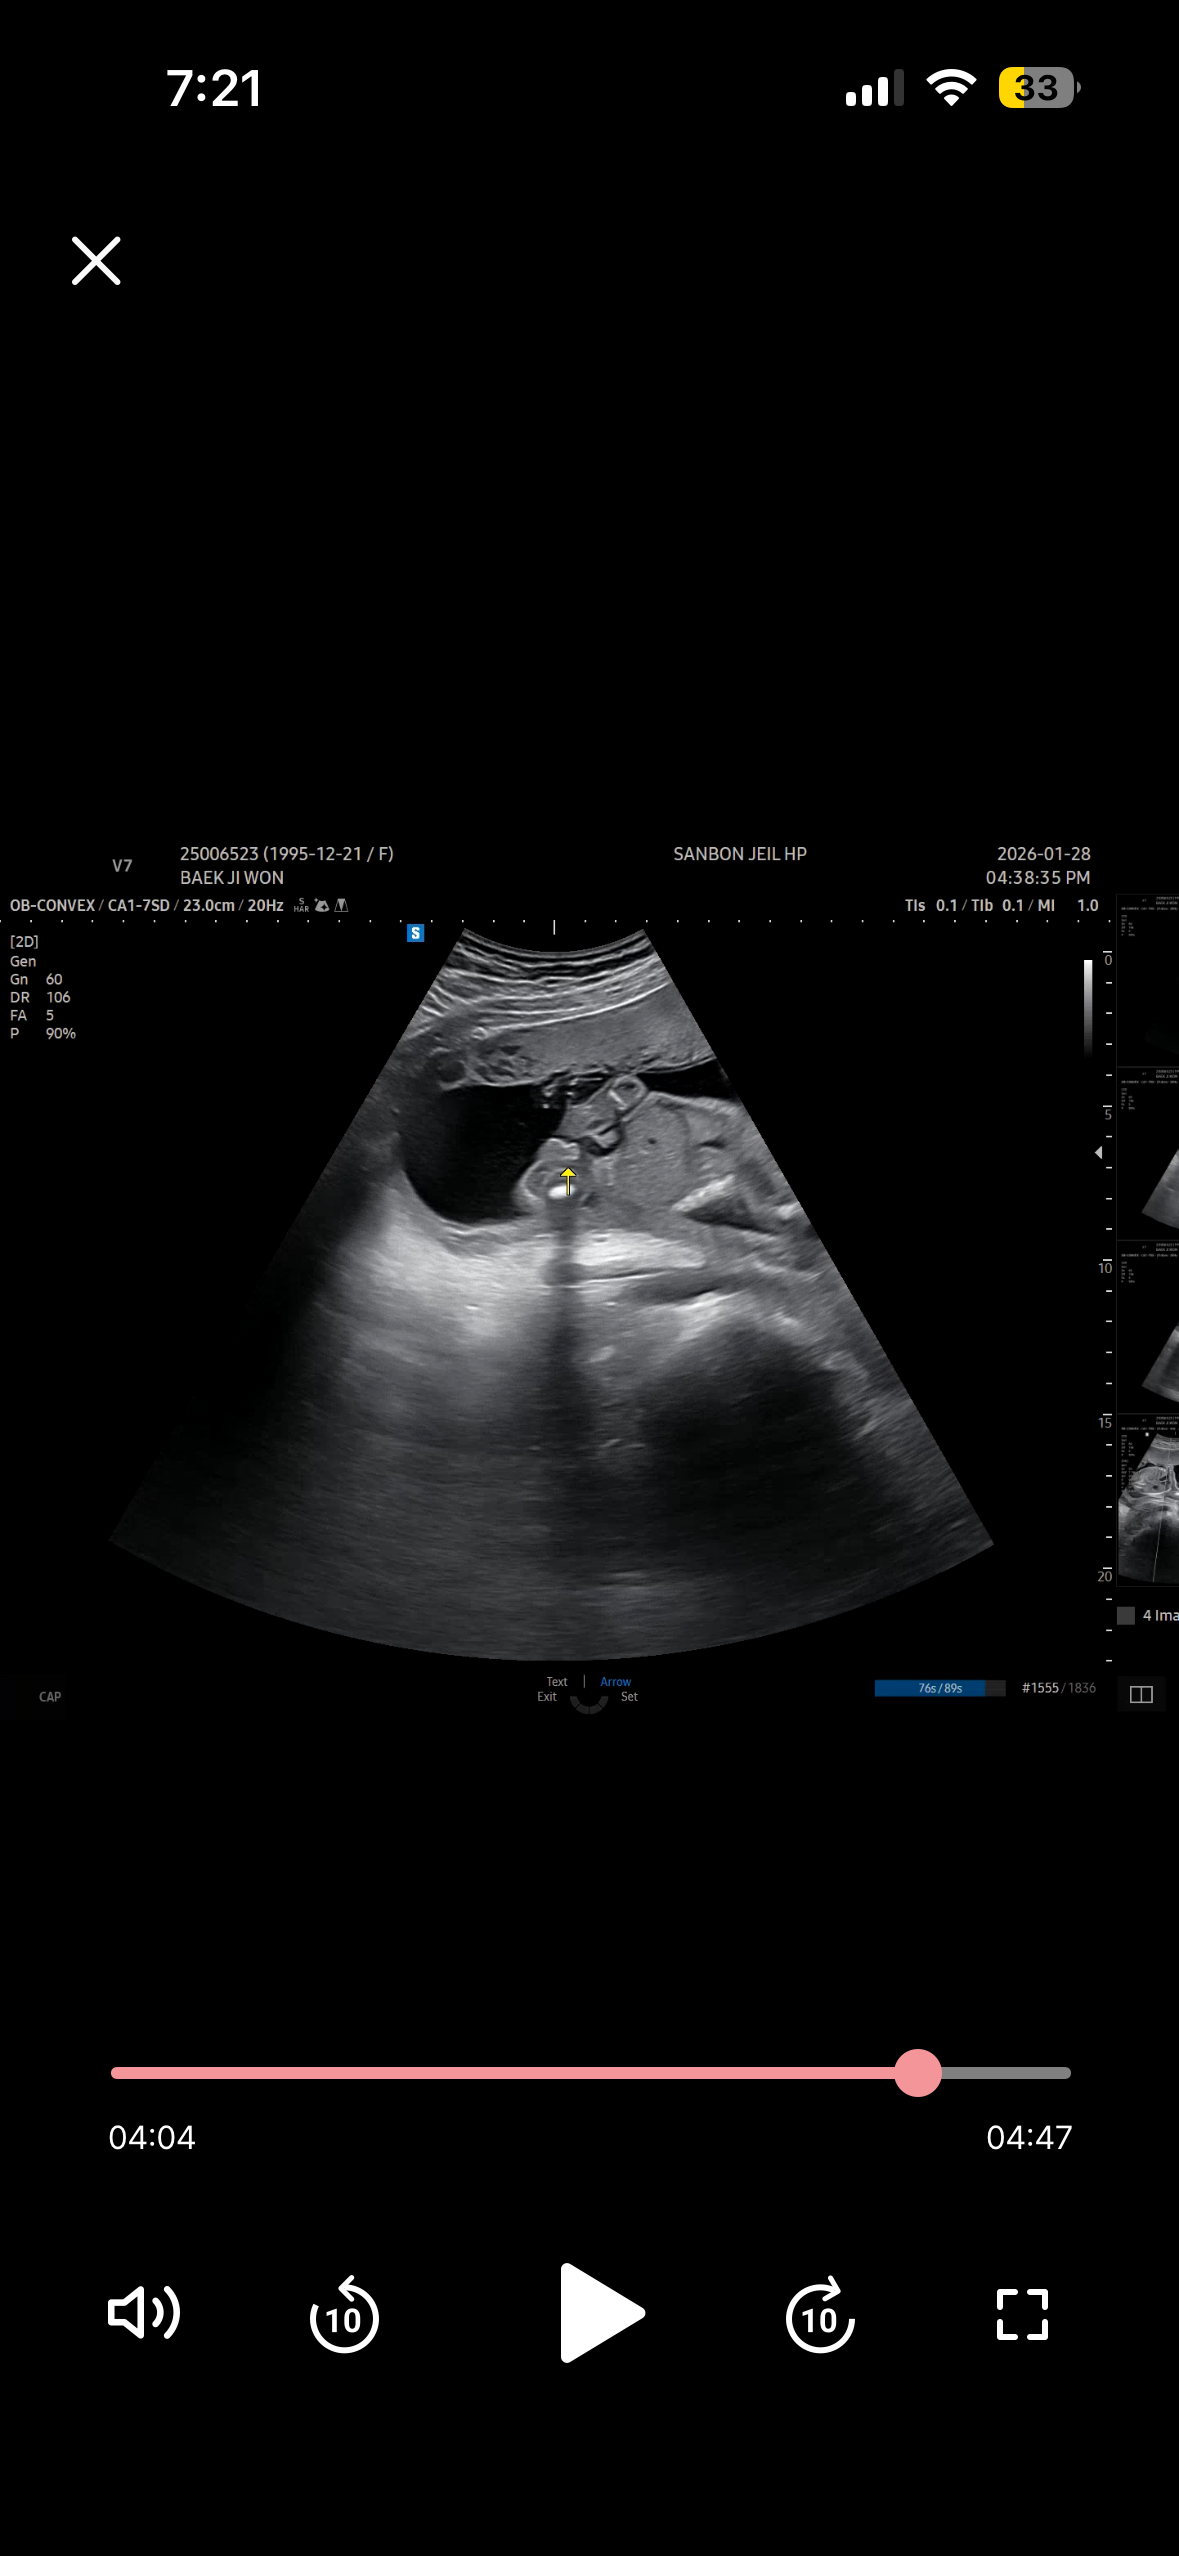

16주차에 뭐가 보인다고 아들을 암시하셨거든요 근데 19주차에 가니 애매하다네요..? 대음순 발달인건지 아직 성기가 덜 발달한건지 애매하다고.! 아들이면 19주차에 무조건 잘 보인다던데.. 뭘까요?! 제일 뭐가 불룩해보이는 사진으로 올려봅니다